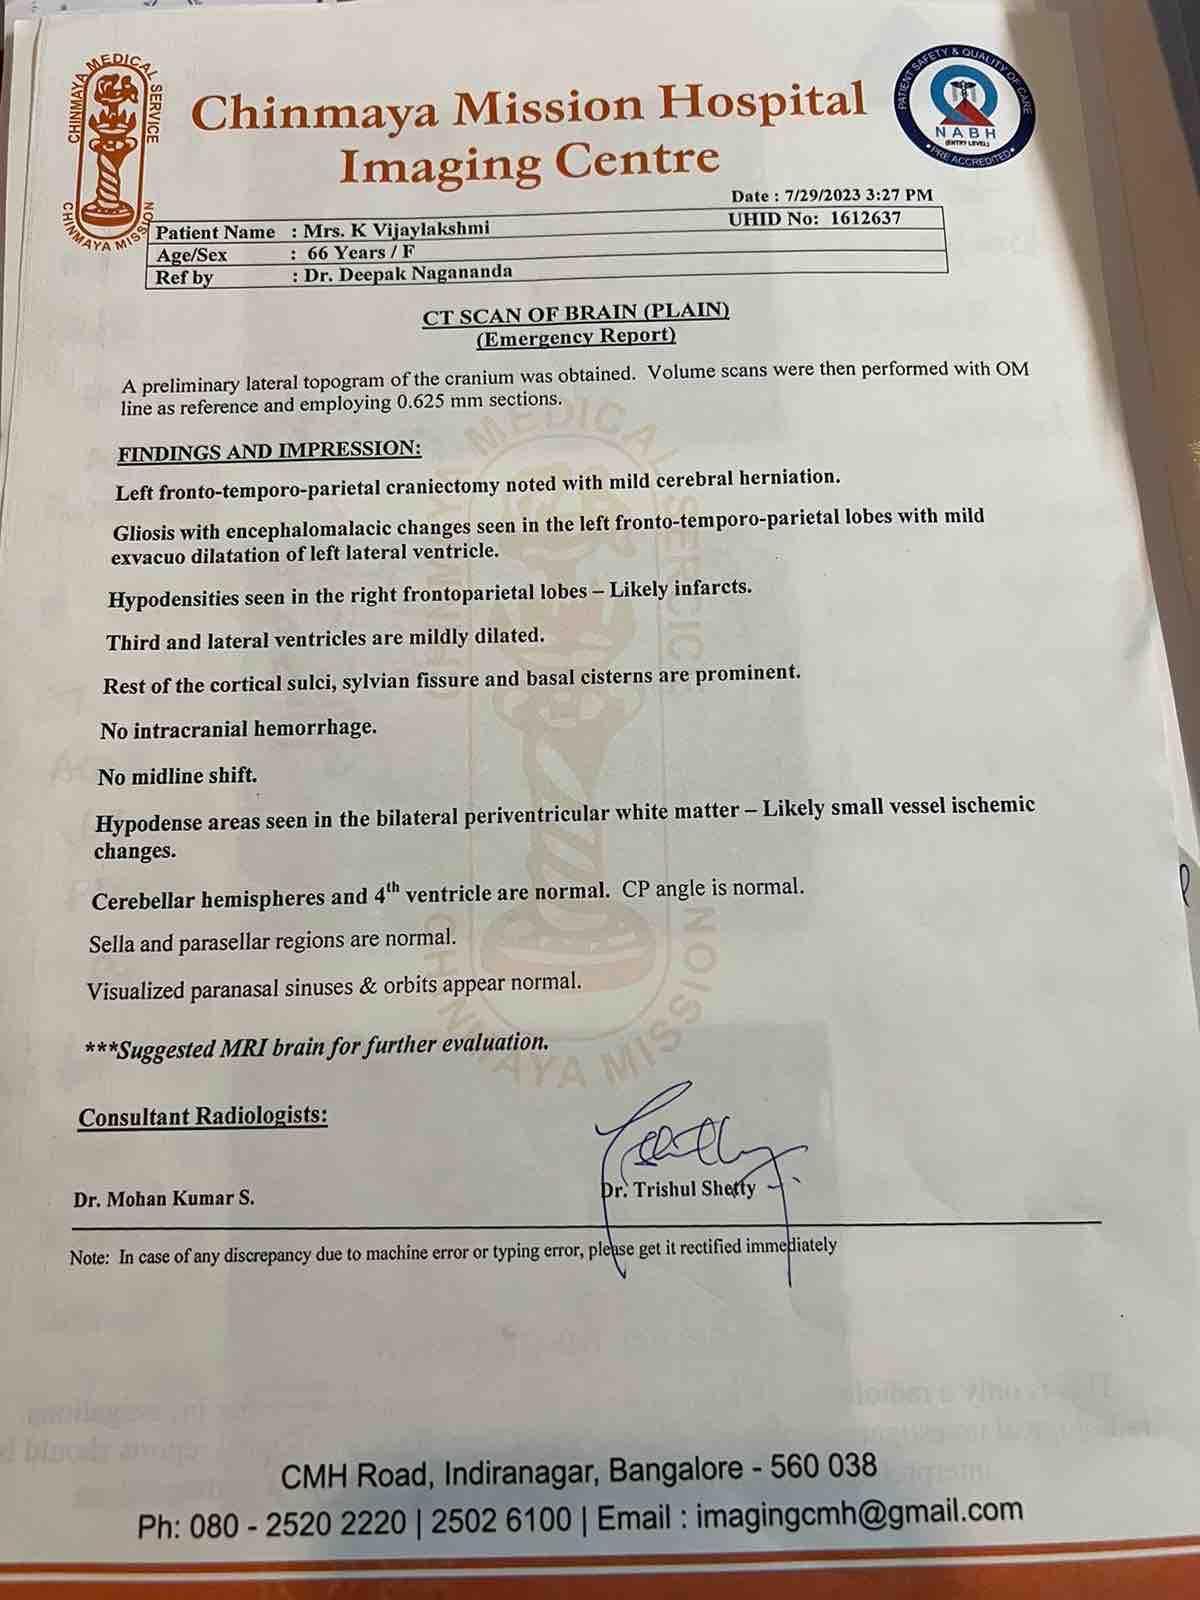

We are reaching out to you today with a heavy heart and a plea for help. Our beloved 66-year-old mother K VIJYA LAKSHMI, has been facing an incredibly challenging journey since 16th May when she had brain stroke & underwent emergency brain and abdomen surgery. Her recovery has been a rollercoaster of ups and downs.

During her hospitalization, she endured multiple complications, including respiratory distress, recurrent severe infections, and even seizure-like activity. Through it all, she has shown immense strength and determination. Still she require three more surgeries to stand on the path of recovery.